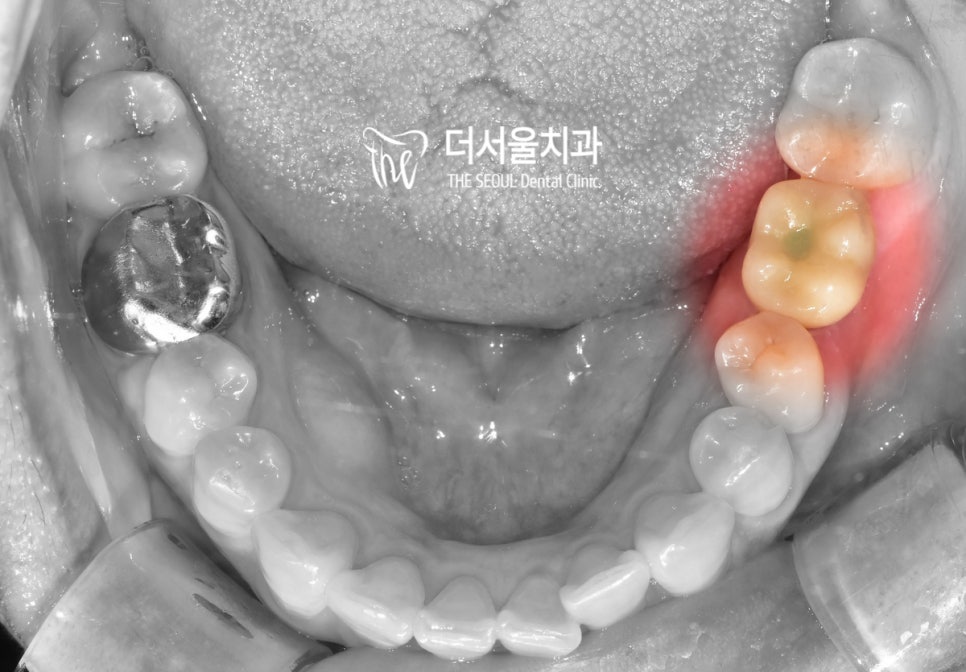

더서울에서는 지르코니아를 사용하여

잃어버린 치아의 외관과 기능을 살려주었으며

미세한 교합, 컨택 조정으로

불편함 없이 사용하실 수 있도록

세밀한 부분까지 확실하게 케어해드렸습니다^^

이로써 최소절개임플란트 과정이

모두 마무리되었네요.

얼마 전, 정기검진을 오셨던 환자분!

이렇게 편할 수가 없다며 기뻐하셨는데요.